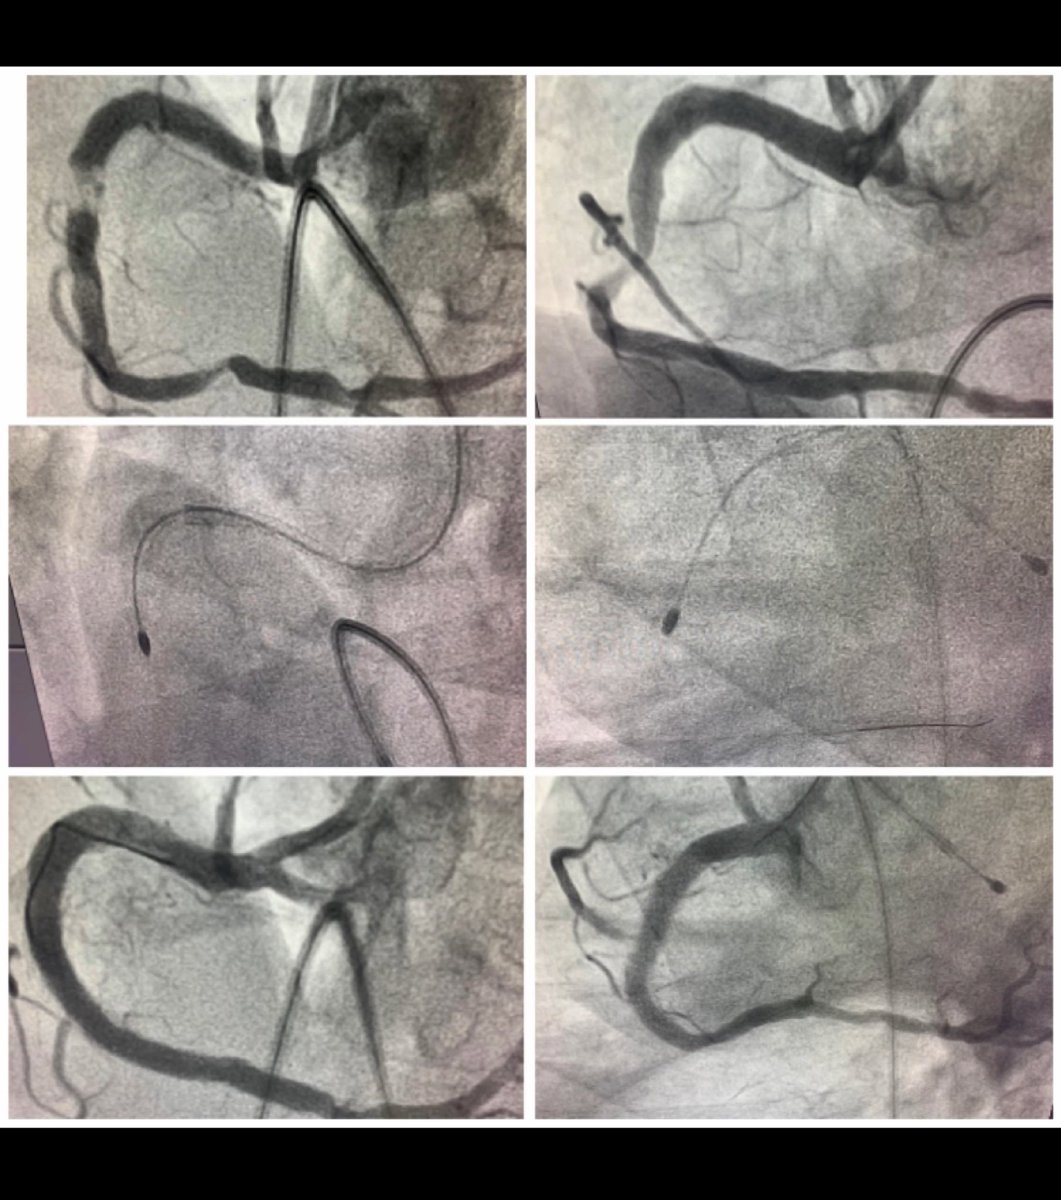

LCx Rotablation is always challanging. Successful LCx Rotablation in 50 Male, class III angina with previous failed attempted PCI. 1.25 Burr at high speed did the trick. excellent result. #CardioTwitter #rotablation #KGMU

DrAshishCardio's tweet image. LCx Rotablation is always challanging. Successful LCx Rotablation in 50 Male, class III angina with previous failed attempted PCI. 1.25 Burr at high speed did the trick. excellent result.